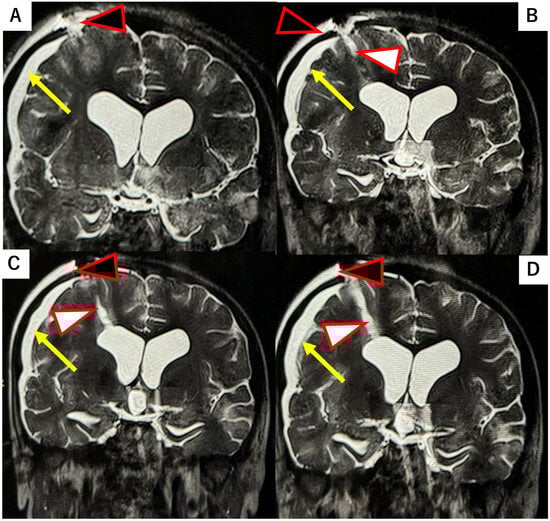

Figure 3.

T2-weighted MRI obtained at 1, 7, 40, and 60 days postoperatively following DuraGen insertion. After neuroendoscopic surgery via the NeuroPort sheath, DuraGen was inserted into the tract. (A) Pre-surgery MRI before DuraGen implantation. (B) A faint T2-hyperintense area is observed along the surgical pathway with the DuraGen implant on postoperative day 1 (POD1). (C) By POD7, the hyperintensity is reduced, indicating absorption of residual cerebrospinal fluid (CSF). (D) At one-month post-op (POD40), the tract that contained DuraGen shows evidence of regenerating brain tissue (yellow arrow). Additionally, new dural formation is apparent at the site of the dural onlay (black arrowhead), with no CSF leakage into subdural or subcutaneous compartments. (E) By POD60, the parenchymal tract has largely healed, appearing comparable to preoperative imaging. Red square: Surgical field where the effect of the DuraGen® plug was assessed.

Several reports have described the use of parenchymal “plugs”, such as oxidized regenerated cellulose (Surgicel®; Ethicon, Inc., Bridgewater, NJ, USA) or gelatin sponge (Gelfoam®; Pfizer Inc., New York, NY, USA), to fill brain parenchymal defects [,]. In this case, we had the opportunity to compare the performance of Surgicel versus DuraGen in preventing CSF leaks and promoting healing, as observed on serial postoperative MRIs. Use of Surgicel was associated with persistent subdural hygroma (fluid collection) and subcutaneous fluid accumulation. In a patient where Surgicel was used to pack the NeuroPort tract, the pathway through the brain parenchyma remained as a fluid-filled defect one month postoperatively, as shown in Figure 4. In that same patient, the tract had not healed even two years postoperatively (Figure 4).

Figure 4.

T2-weighted MRI at 30 days and two years postoperative in a case where Surgicel® was used to pack the NeuroPort tract (with schematic diagram inset). (A–C) Along with the NeuroPort tract, a persistent fluid-filled parenchymal defect (white arrowhead) is visible at 30 days post-op, with reflux of CSF back into the ventricular system. This is associated with the formation of a subdural hygroma (yellow arrow). CSF accumulation is also evident in the subcutaneous tissue (effusion from the dural defect, black arrowhead). (D) Little to no healing of the tract is observed even at two years follow-up.

In contrast, the case using DuraGen showed no subdural or subcutaneous fluid effusion. The parenchymal defect gradually healed and was replaced by tissue of iso-intense signal to surrounding brain, with minimal granulation tissue. This regenerative process is evident in MR images at postoperative days 1, 7, 40, and 60 (Figure 3), which show the initial tract and faint high intensity along the pathway (day 1), partial absorption of CSF by day 7, and progressive parenchymal healing by days 40 and 60, along with dural restoration at the burr hole site.